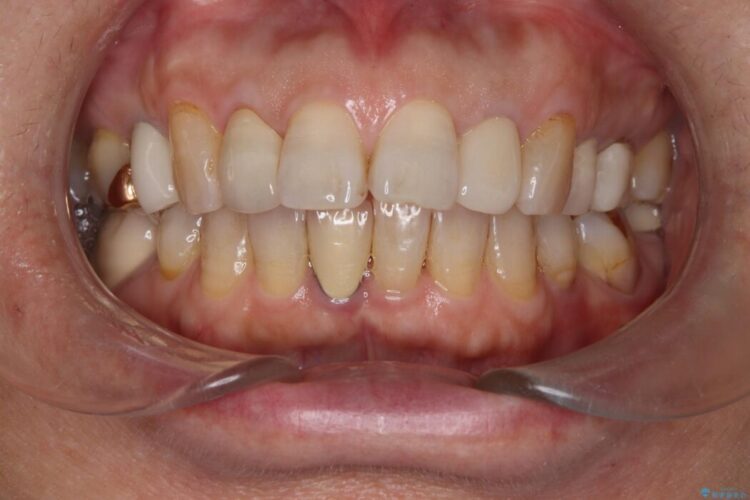

破折したセラミックインレーのやり替え

他院で装着されたセラミックインレー(MOD窩洞)が破折したとご来院されました。

治療期間(治療回数):1ヶ月(2~5回) | 概算治療費:15.4万円(税込)(オールセラミッククラウン14.3万円+仮歯1.1万円)